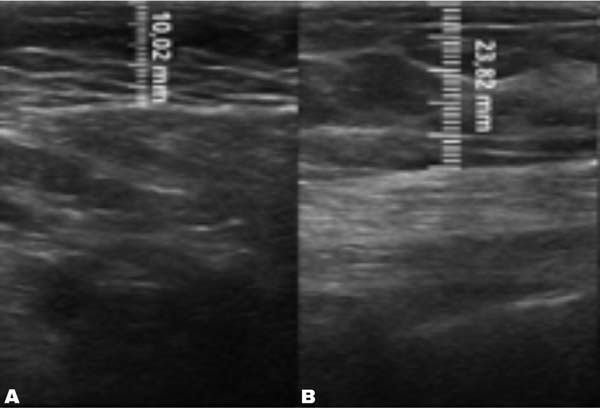

A mensuração da espessura do tecido subcutâneo é realizada de forma vertical, do ponto mais alto (logo na transição da epiderme) ao ponto mais baixo (na transição com o tecido muscular) da espessura de tecido subcutâneo. Essa medida é de fácil reprodutibilidade para quem possui aptidões básicas em ultrassonografia. ►Fig. 2. A medida da espessura de tecido subcutaneo na mama lipoenxertada foi realizada no pré- e pós-operatório imediato da lipoenxertia, e após 15,30, 90 e 180 dias. As medidas foram feitas atraves da ultrassonografia, em milimetros, medindo a distancia vertical do ponto mais superior (proximo à epiderme) ao mais inferior (proximo à musculatura adjacente) do tecido subcuta neo no ponto previamente definido. Foi utilizado equipamento de ultrassom modelo GE, LOGIQP6 (GE Healthcare) com uso de sonda linear de 11L com faixa de frequencia de 12 a 6 MHz, operado por cirurgião com pós graduação lato sensu em ultrassonografia geral. ►Fig. 3.

No grupo enxerto decantado, a reducãomédia, comparando-se a espessura inicial apos lipoenxertia, foi de 9,90% no 15° dia, 19,27% no 1° mes, 23,59% no 3° mes e 26,36% no 6° mes. No grupo enxerto filtrado, a reducao media, comparando-se a espessura inicial apos lipoenxertia, foi de 7,74% no 15° dia, 14,85% no 1° mes, 20,67% no 3° mes e 22,80% no 6° mes. ►Fig. 6. A evolução ao ultrassom da espessura do tecido subcutâneo antes e depois da lipoenxertia pode ser vista nas ►Figs. 7-8. Os resultados de pré-e pós-operatório de uma paciente de cada um dos grupos estão exibidos nas ►Figs. 9-10.